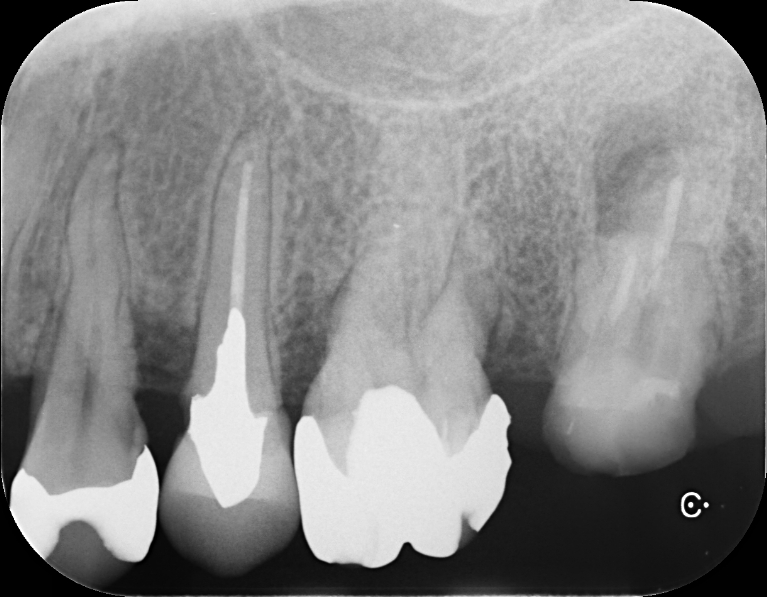

Case1

術前

術後

| 治療名 | 再生療法 |

|---|---|

| 治療説明 | 右上6,7、左上5,6に重度の歯周病があり、通常の歯周治療でも改善しませんでした。歯周組織再生療法を行い、吸収してしまった骨を再生し、今後の歯周病の進行リスクを減らす事ができました。 |

| 治療回数・期間 | 6ヶ月 |

| 副作用とリスク | 手術後に出血、腫脹、疼痛が生じることがあります。手術後は術部の創傷安定のためにブラッシング制限、食事制限があります。手術が複数回となることがあります。 |

| 料金(税込) | 歯周組織再生療法:220,000円(左右2箇所:440,000円) セラミッククラウン2本・ブリッジ1箇所:550,000円 総額:990,000円 |